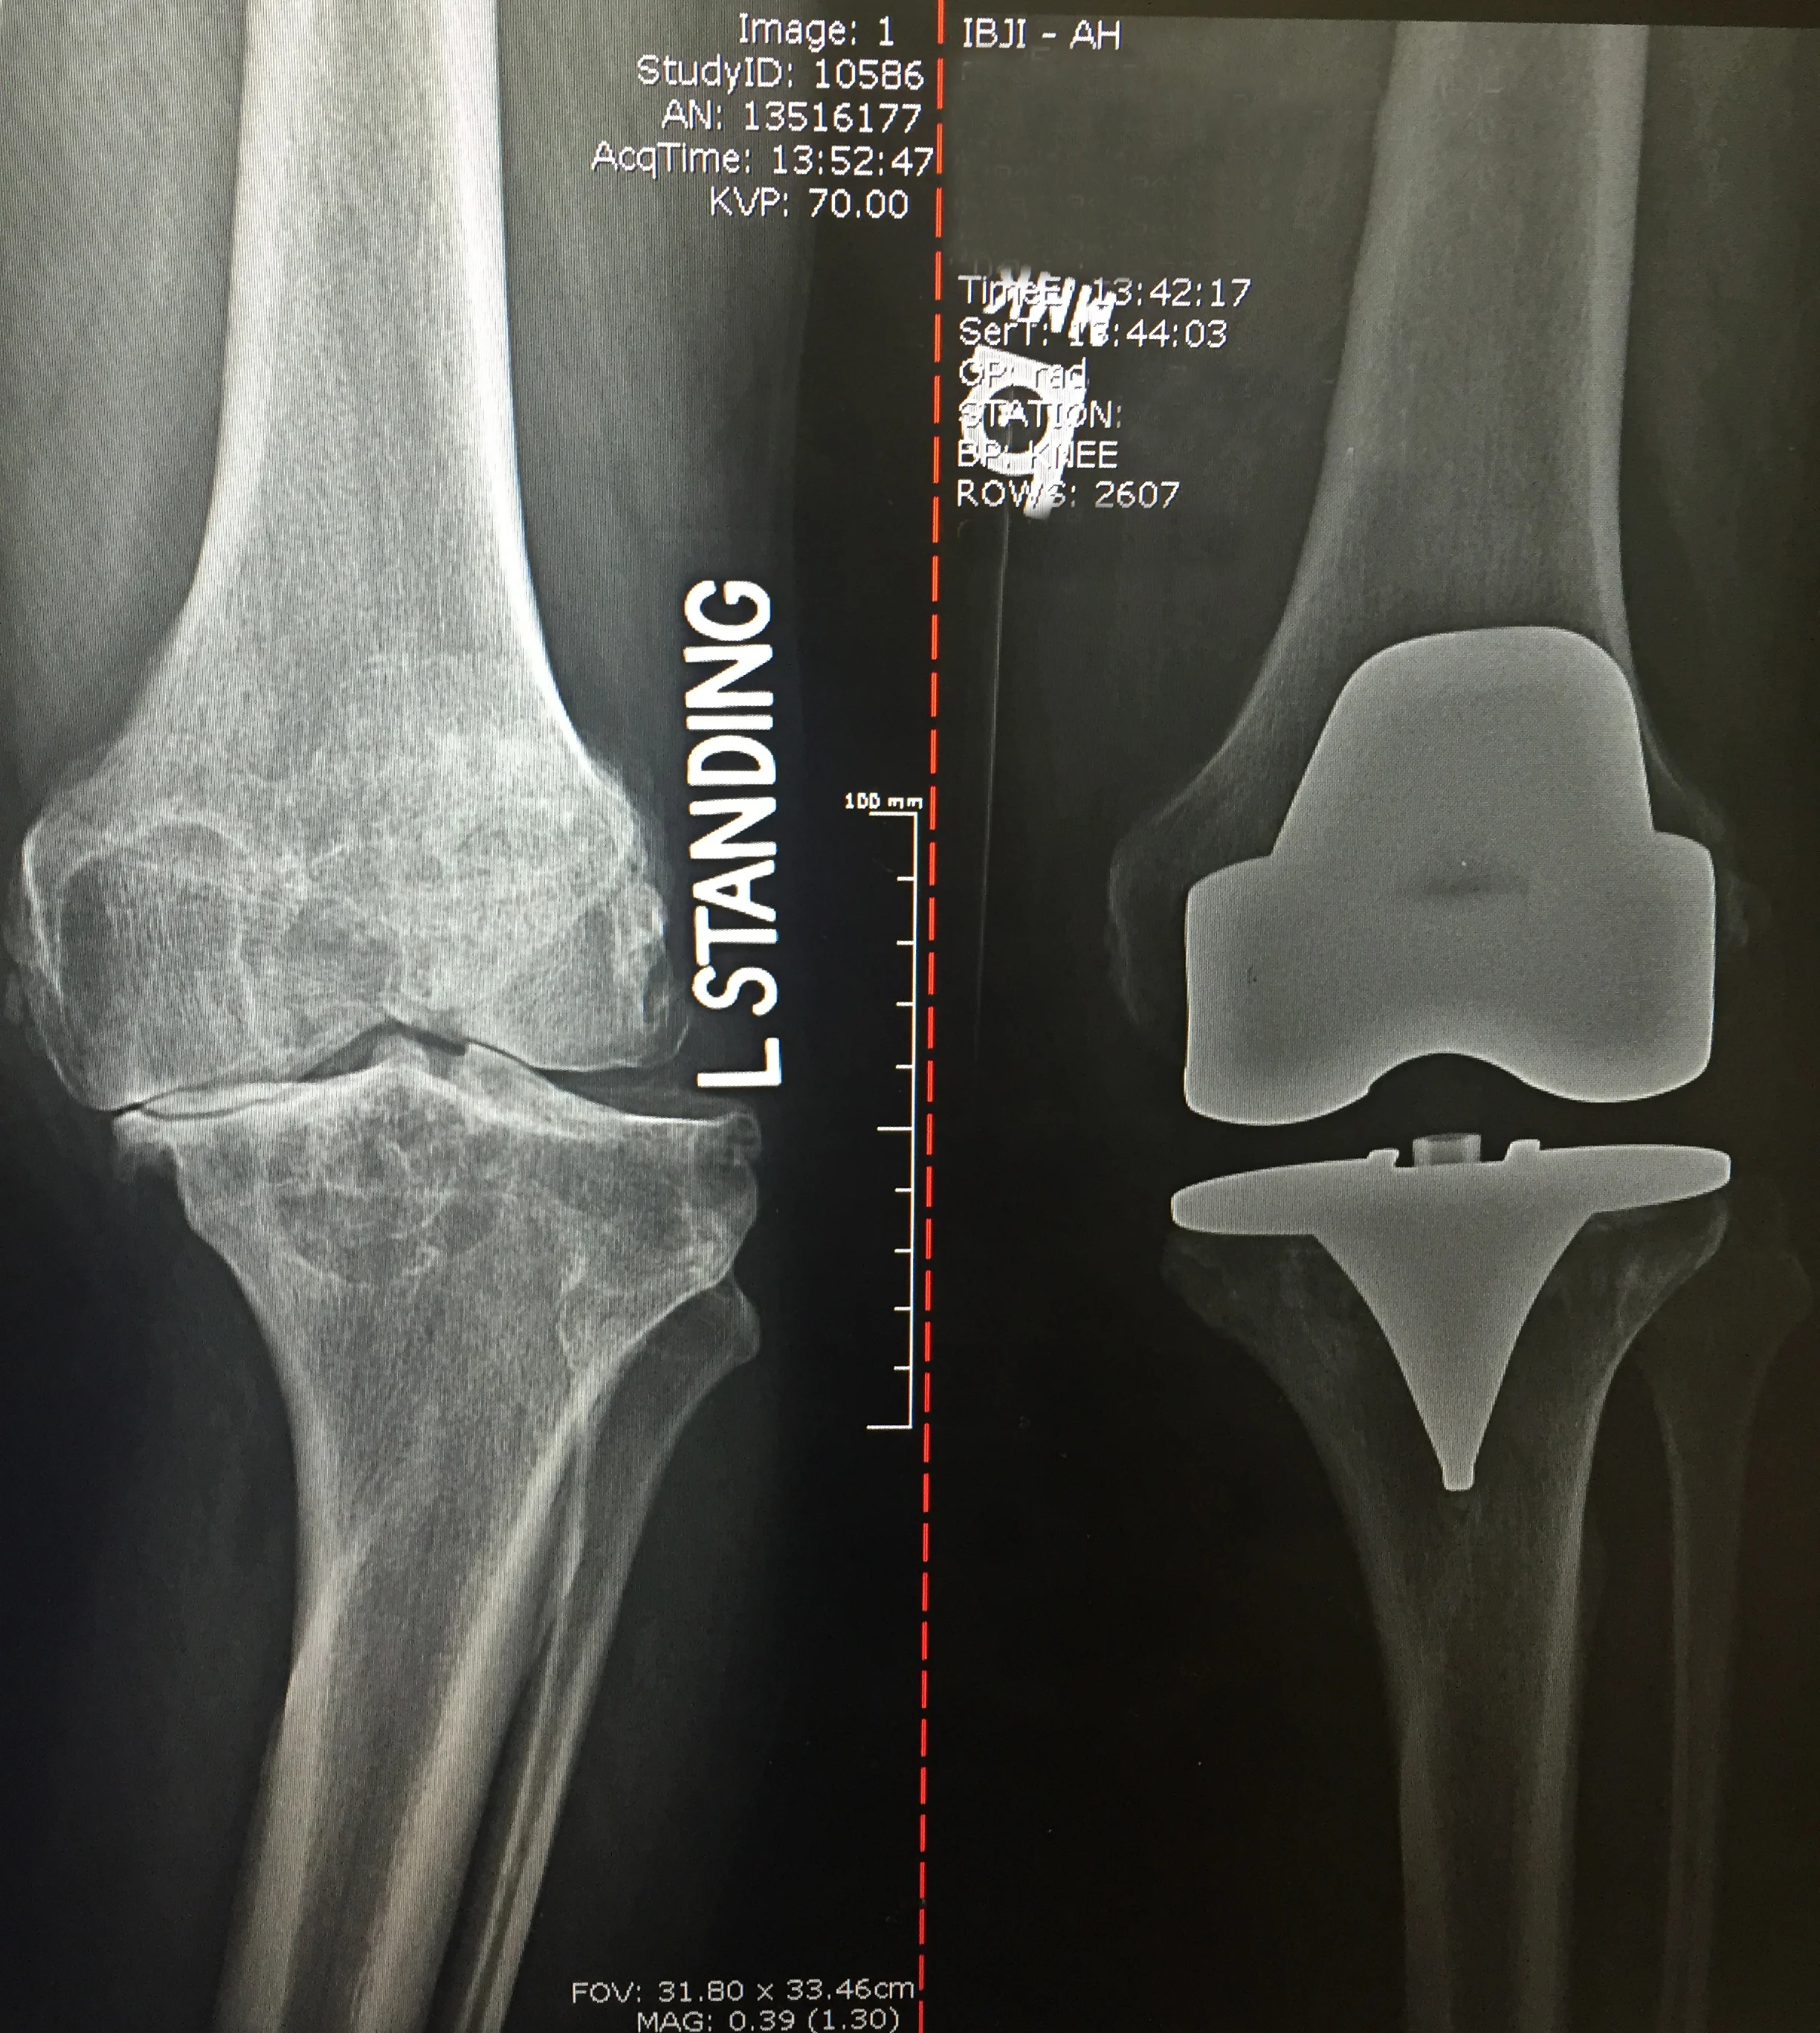

Before: bone on bone - bowed

After: Total Knee Replacement - straight

OMNI

Before: Bone on bone arthritis affecting only the medial (inside) compartment

After: Partial Knee Replacement

BIOMET OXFORD PKR